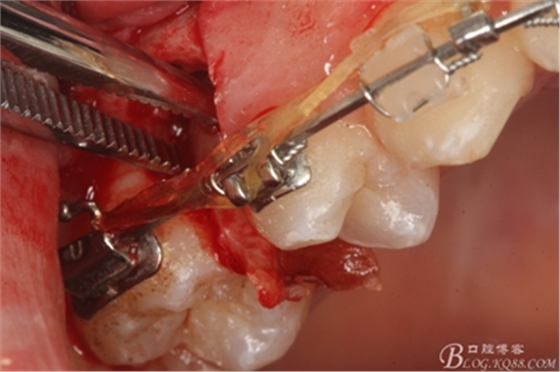

圖17.血管鉗取出近中部分15牙根

圖18.取出近中部分后,接著挺松15牙根的遠(yuǎn)中部分

圖19.挺松后,15的遠(yuǎn)中部分仍從合面狹小間隙通過取出。